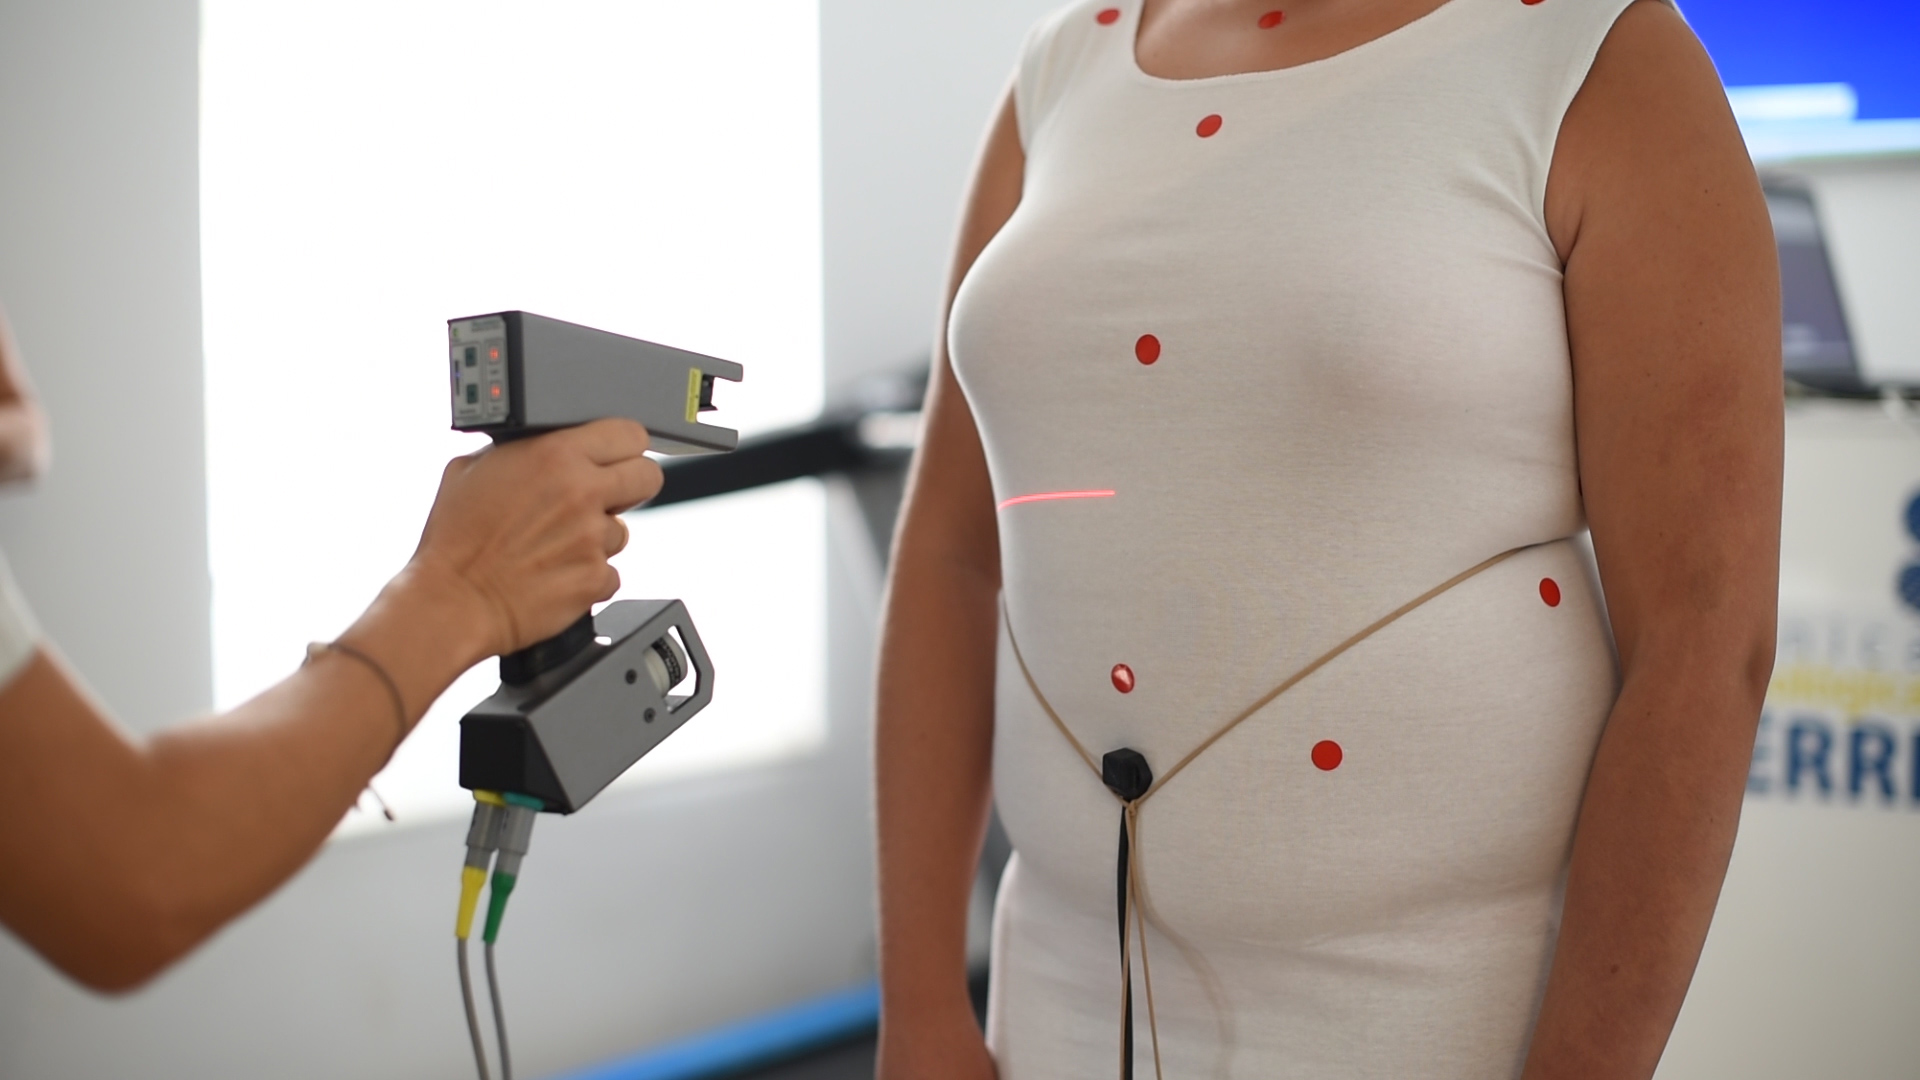

Nuestro trabajo en la ortopedia consiste en tomar medida del paciente mediante láser CAD-CAM, para diseñar el corsé, creando un archivo de su forma escaneada, y a partir de aquí se fabrica la ortesis mediante positivo fresado.